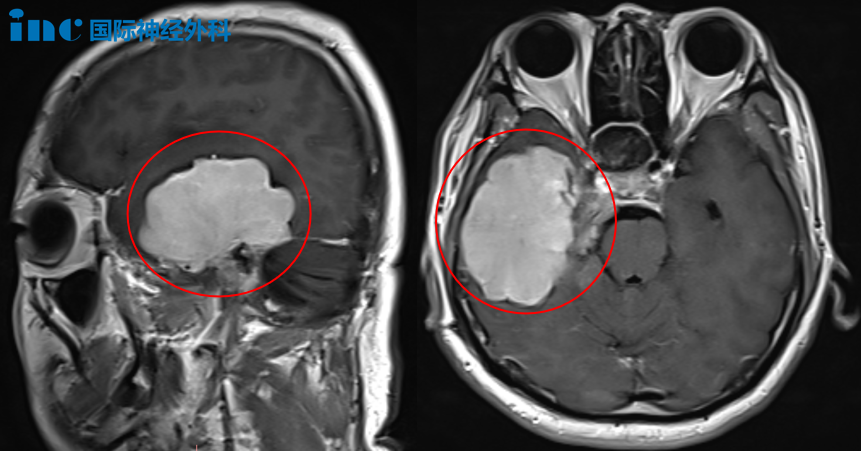

三年后复查MRI显示肿瘤显著增大,侵犯右侧岩斜区、右颞底、乳突区及右侧小脑幕,甚至将三叉神经和滑车神经完全包裹。其中右颞叶病灶达32×31×25mm。一年后,脑膜瘤继续生长,右颞叶病灶增至惊人的67×49×47mm!